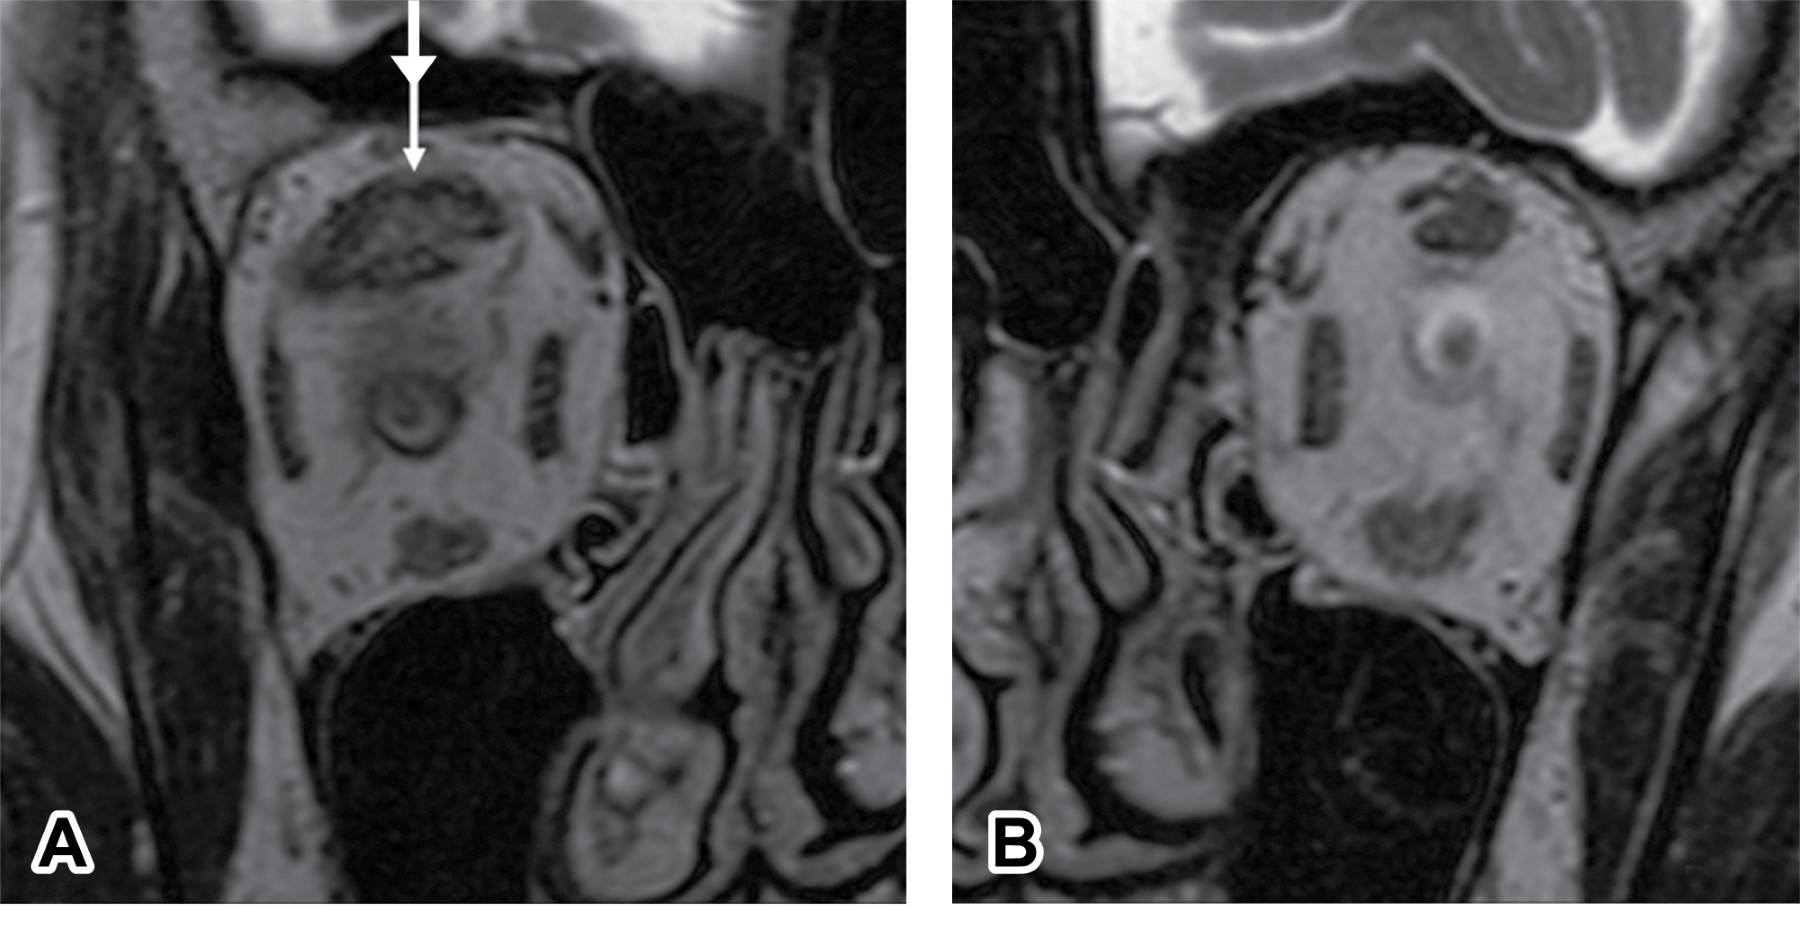

En la OT se produce aumento de volumen de los músculos extraoculares, de la grasa y del tejido conectivo por depósito de glucosaminoglicanos y de linfocitos T CD4+, macrófagos y linfocitos, lo que afecta al tejido conectivo o septos fibrosos de los músculos extraoculares que parecen ser los sitios involucrados en la fibrosis y cicatrización que se manifiesta como exoftalmos, alteración de la motilidad, congestión venosa, compresión en el ápex y neuropatía (Figuras 1 y 2).

Figura 1

Figura 2